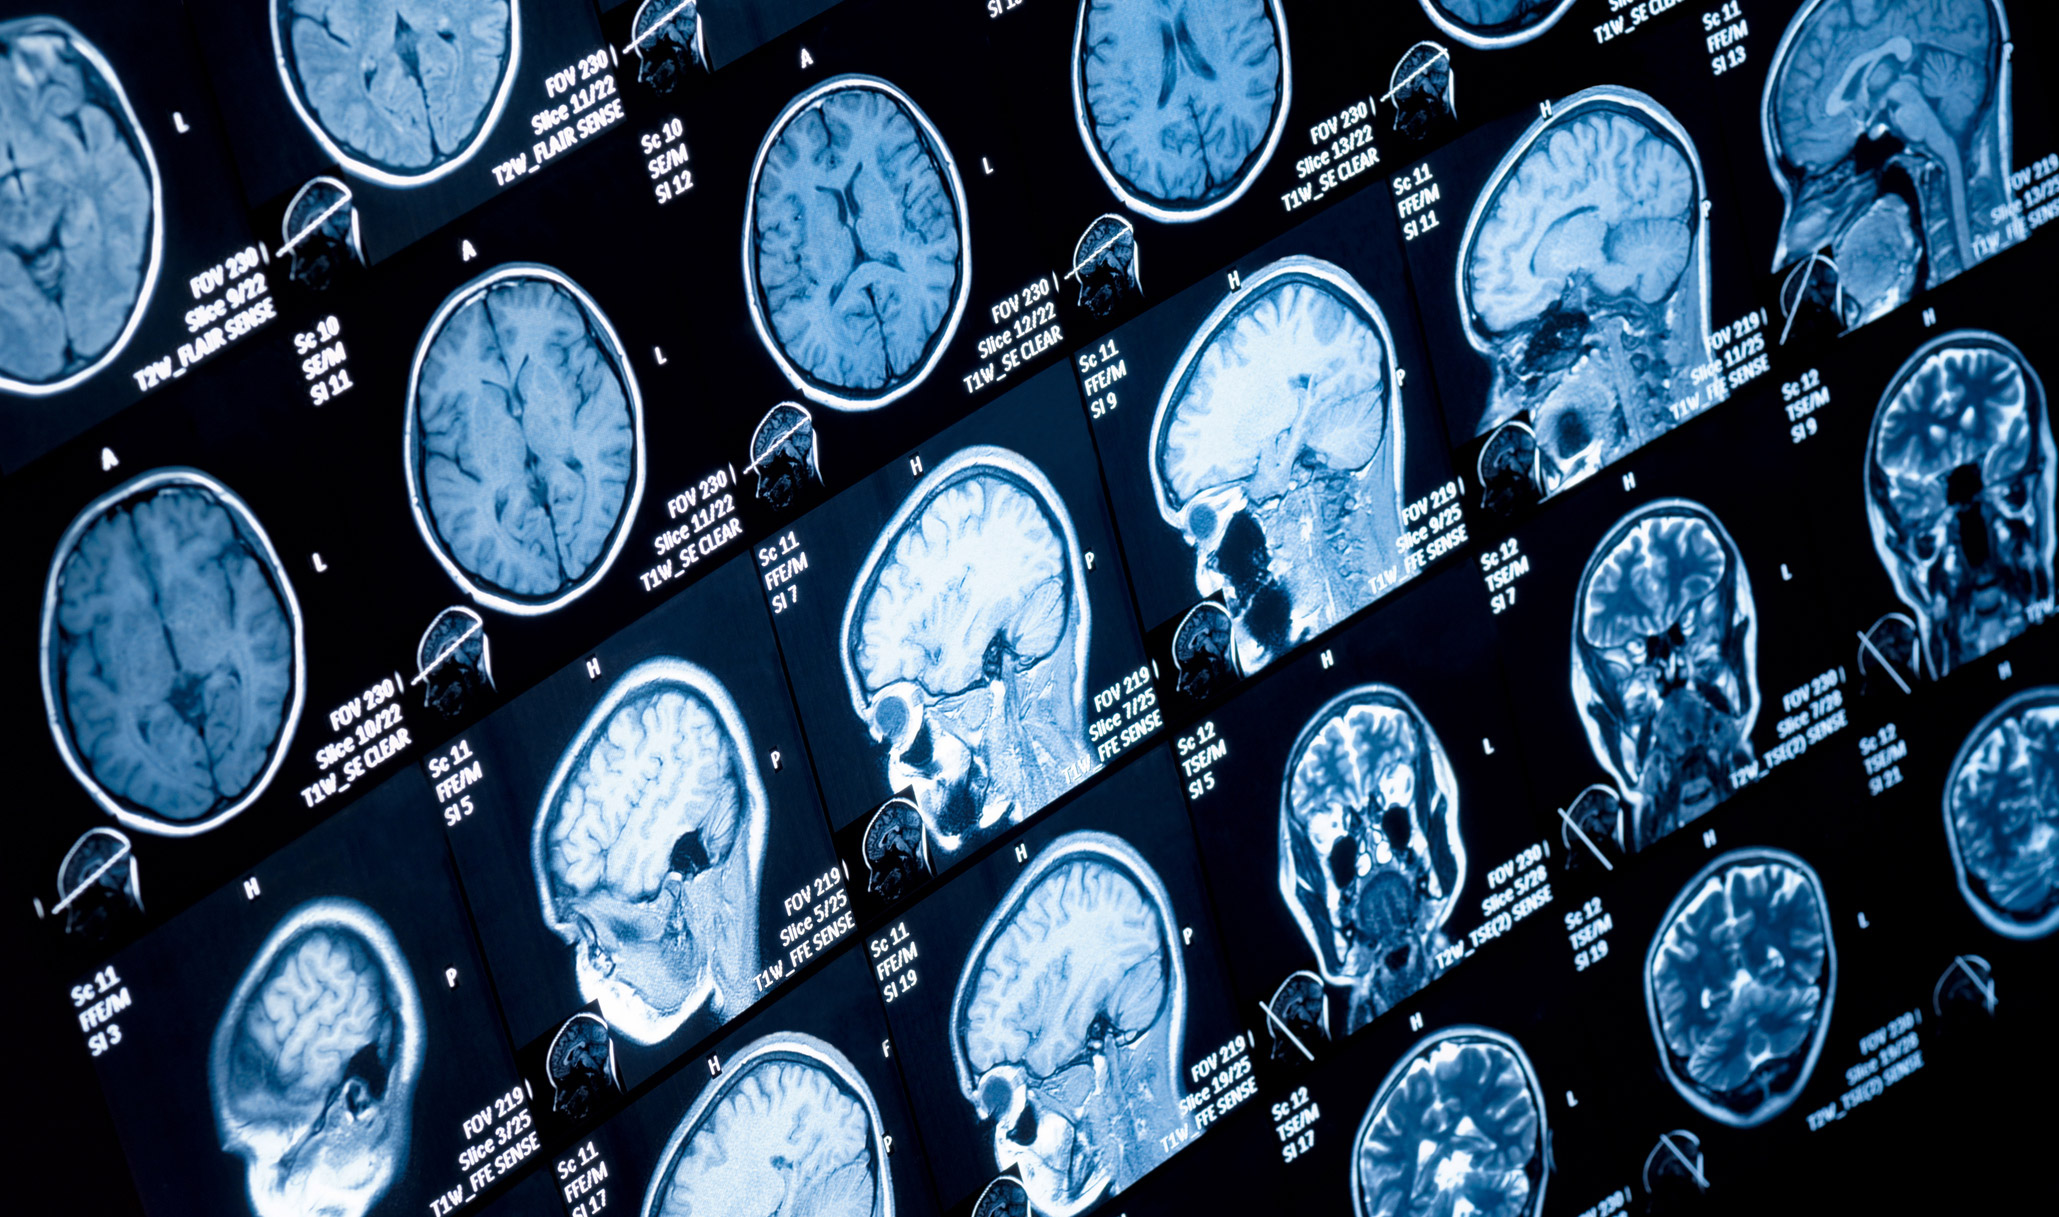

New data has been made available which will help develop “wiring diagrams” that may ultimately improve understanding of a range of brain disorders.

The international team of researchers led by scientists at the Child Mind Institute, USA and including scientists from the Institute of Neuroscience at Newcastle University, UK has released the first open-source data sets of non-human primate brain imaging.

In a new study, An Open Resource for Non-human Primate Imaging published in the journal Neuron, the researchers present details about the rationale, design, and procedures for the PRIMatE Data Exchange (PRIME-DE) consortium, an open science resource for the neuroimaging community that aims to aggregate and share anatomical, functional and diffusion MRI data sets from laboratories around the world.

The goal is to accelerate the development of a map of the neural connections in the non-human primate brain -- and, ultimately, the human brain -- in an effort to develop biomarkers for mental health disorders and other brain disorders and diseases.